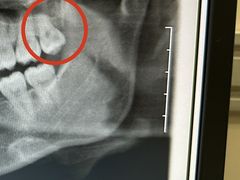

• 上海市徐汇区口腔医院

• -上海市徐汇区口腔医院